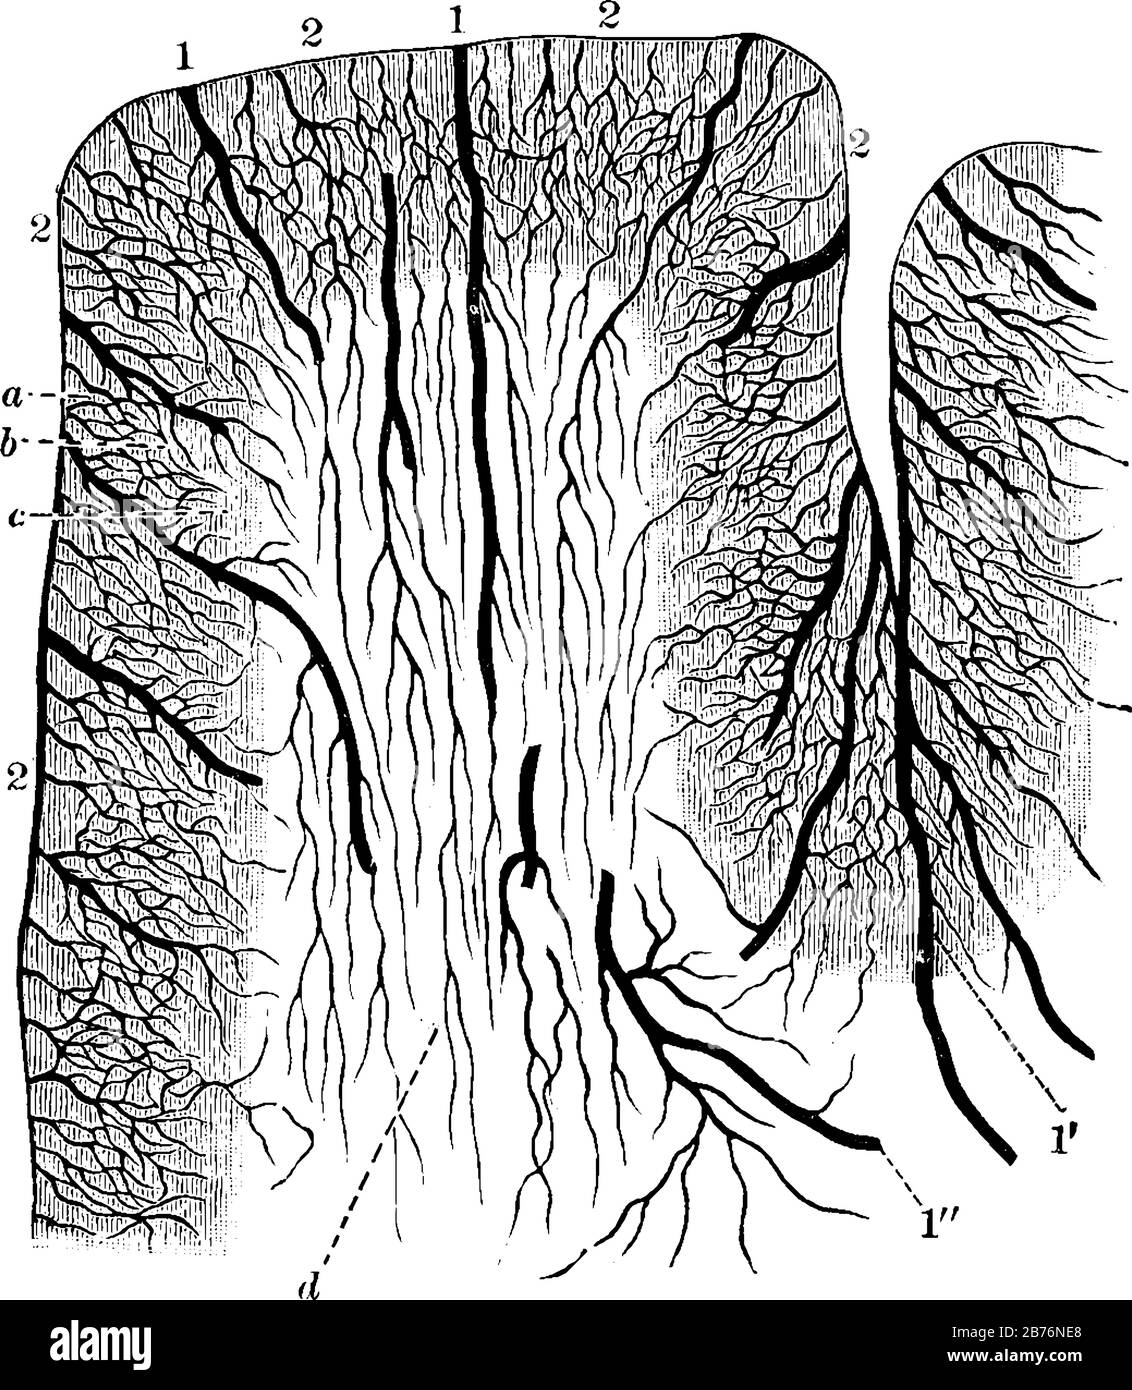

RF2B76NE8–Diagramma delle Arterie Corticali responsabili della fornitura di sangue alla corteccia cerebrale, disegno di linee d'annata o illustrazione dell'incisione.

RFEW9JFK–Base del cervello, vintage illustrazioni incise. Al solito Dizionario medicina dal dr. Labarthe - 1885.